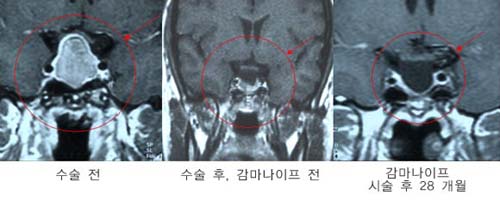

ºñ±â´É¼º

°Å´ë³úÇϼöü Á¾¾çÀ¸·Î ÀÎÇÑ ½Ã·Â»ó½ÇÀ»

ÁÖ¼Ò·Î ³»¿øÇÑ È¯ÀÚÀÇ MRI ÀÀ±Þ

³ú¼ö¼úÀ» ÅëÇØ Á¾¾çÀ» Á¦°ÅÇÑ ÈÄ ³²Àº

Á¾¾ç¿¡ ´ëÇØ °¨¸¶³ªÀÌÇÁ ¹æ»ç¼± ¼ö¼úÀ»

½ÃÇàÇÏ¿© ¿ÏÄ¡µÊ

¹Ì¼¼³úÇϼöü

Á¾¾çÀ¸·Î ÀÎÇÑ Äí½ÌÁõÈıºÀ¸·Î °¨¸¶³ªÀÌÇÁ

¹æ»ç¼± ¼ö¼úÀ» ½ÃÇàÇÑ È¯ÀÚÀÇ MRI. ¹æ»ç¼±

¼ö¼ú 13°³¿ù ÈÄ ¿ÏÄ¡µÈ ¼Ò°ßÀ» º¸¿´´Ù